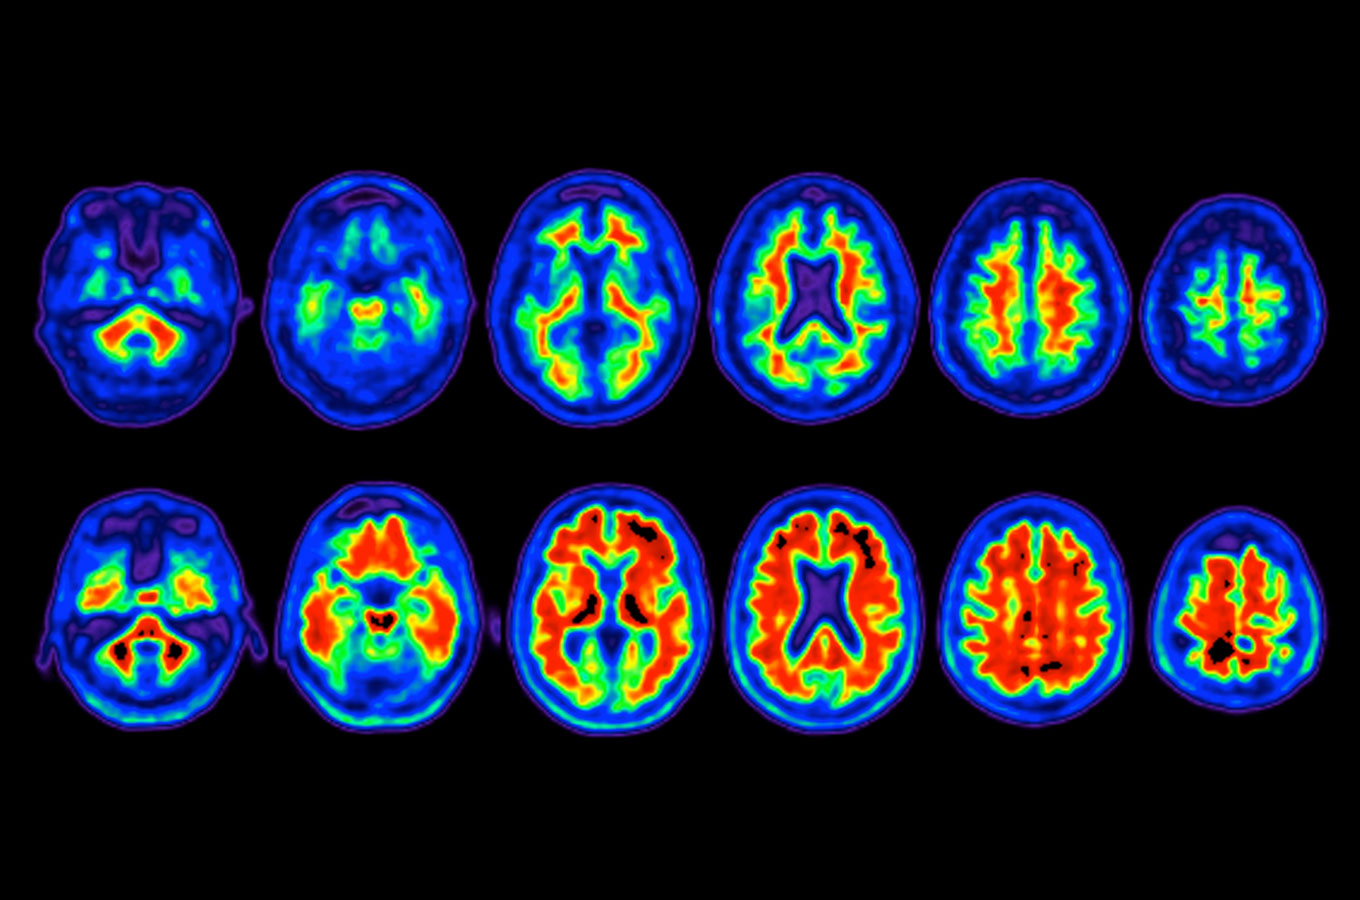

negative amyloid PET scan of brain

Top row shows negative amyloid PET scan of brain. Bottom row shows positive amyloid PET scan, with illumination of amyloid plaques, indicative of Alzheimer's disease. Images courtesy of IDEAS study and Rabinovici lab at UCSF